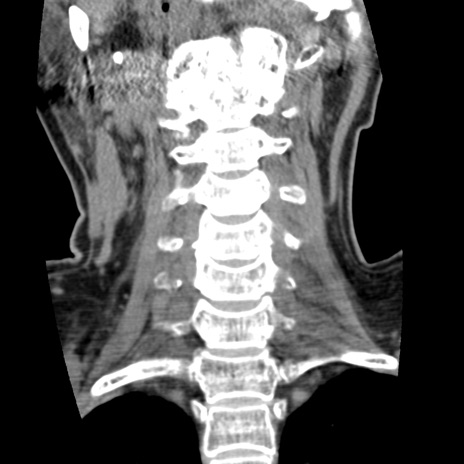

症例50 頚椎CT(冠状断像)

【症例】60歳代女性

【主訴】後頭部〜右後頸部にかけての痛み

【現病歴】本日飲食店でコーヒーを飲んでいたところ、突然後頭部〜右後頸部にかけて痛みが出現し、右上肢の感覚障害を伴ったため救急要請。

【身体所見】脳神経学的に明らかな異常所見を認めず。右上肢に軽度の感覚障害あり。

異常所見と診断は?

頚椎CT